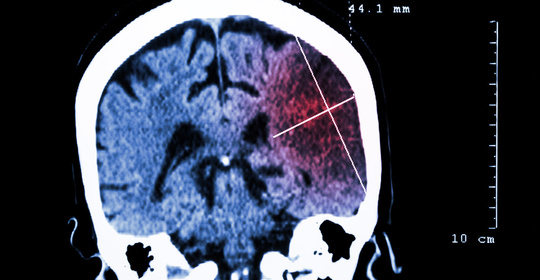

腦中風後遺症的症狀、前兆、治療和預防

腦溢血後遺症的症狀、前兆、治療和預防

腦血管破裂後遺症的症狀、前兆、治療和預防

腦梗塞後遺症的症狀、前兆、治療與預防

腦出血引流手術後遺症的症狀、前兆、治療和預防

腦栓塞後遺症的症狀表現、前兆、治療與預防